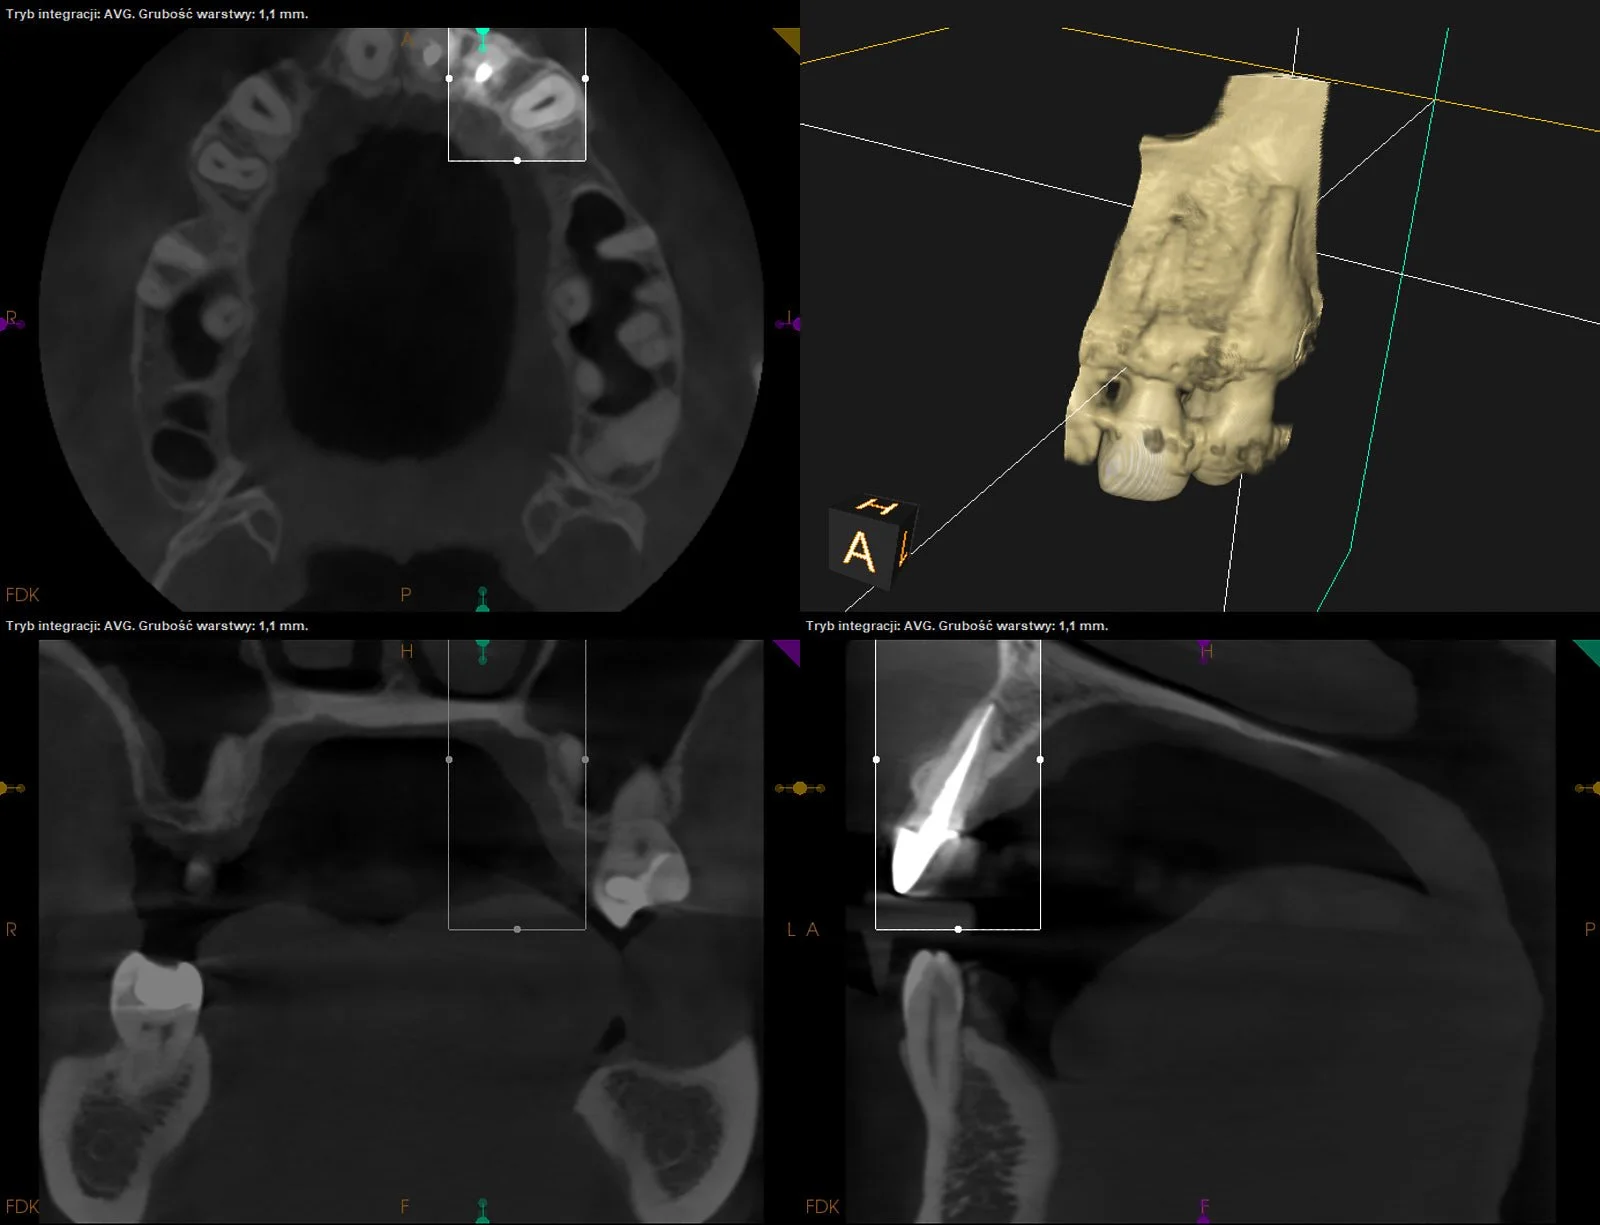

CASE STUDY IX

Usunięcie ankera zacementowanego na cement kompozytowy oraz reendo d.45 wraz z wykonaniem odbudowy adhezyjnej.